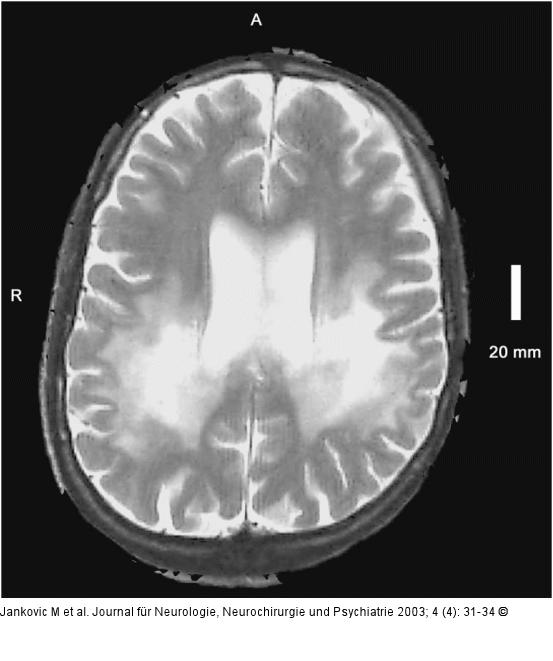

Abbildung 1: Adrenomyeloneuropathie Axiale T2 des Gehirns: Ausgeprägte hyperintense Signalveränderungen im Centrum semiovale erkrankungstypisch im dorsalen Anteil. |

Axiale T2 des Gehirns: Ausgeprägte hyperintense Signalveränderungen im Centrum semiovale erkrankungstypisch im dorsalen Anteil. |